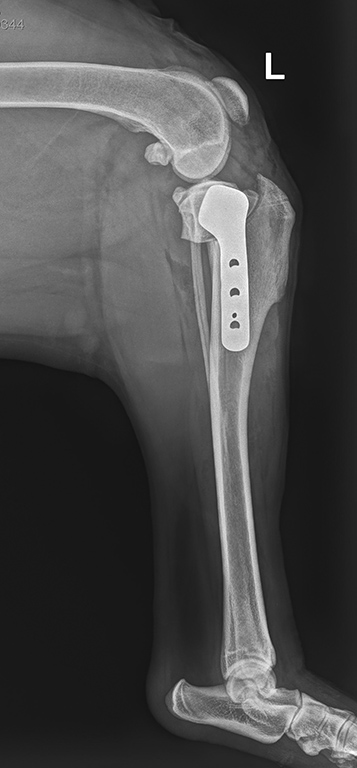

Die vermutete Diagnose wird röntgenologisch bestätigt (Gelenkfüllung, Schublade/Subluxation, typische Muster der Arthrose) und nur in seltenen Fällen ist aufwändigere Diagnostik zusätzlich notwendig (MRT, Arthroskopie, Gelenkpunktion).

Als Operationsmethode der Wahl für Hunde und Katzen aller Größen hat sich bei uns die sogenannte TPLO (Tibial Plateau Leveling Osteotomy) Operation etabliert. Diese Methode ermöglicht dynamische Stabilisation und ist auch nach eventueller Entfernung der Implantate unverändert wirksam.